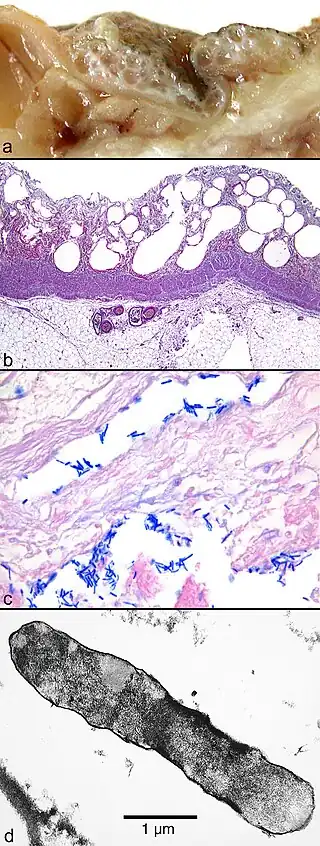

a,b) Gas gangrene -

Plain X-Ray of a patient with gas gangrene of left leg -

Muscle biopsy examined under the microscope (haematoxylin-eosin stain, zoom 100×): the large white areas between the muscle fibers are due to gas formation. -

Gram stain of a muscle biopsy showing Gram-positive, rod-shaped, anaerobic, spore-forming bacteria in the infected muscle tissue: The result is highly compatible with an infection with C. perfringens.